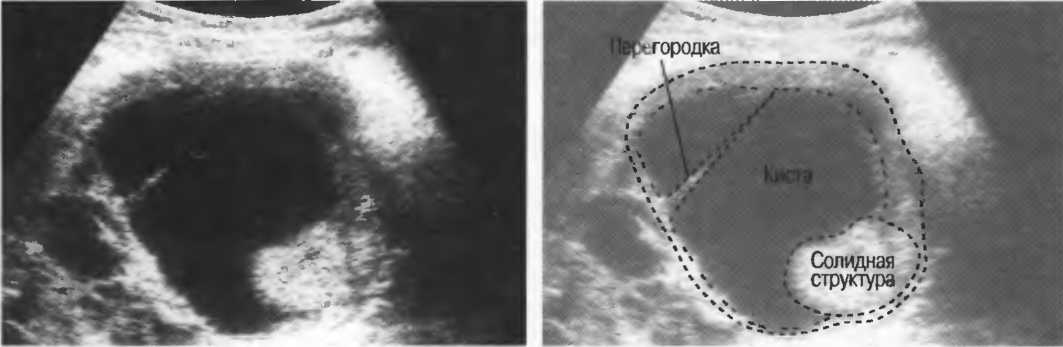

Артефакты могут определяться в любой кистозной структуре (такой, например, как мочевой пузырь или желчный пузырь) и чаще определяются ближе кпереди, становясь менее выраженными на глубине. Они исчезают или меняют свой характер при изменении положения датчика. Но истинные структуры в кисте, такие как перегородки, сохраняют свое местоположение независимо от положения датчика. Истинные отражения имеют место при наличии сгустка крови, гноя, некротической взвеси, и все это чаще визуализируется по задней стенке: если эти структуры не фиксированы к стенке, они изменяют свое положение при перемене положения тела пациента (рис. 16).

Рис. 16а. Злокачественная киста яичника: крупная киста с внутренней перегородкой, которая остается в прежнем положении при сканировании пациентки в различных положениях.